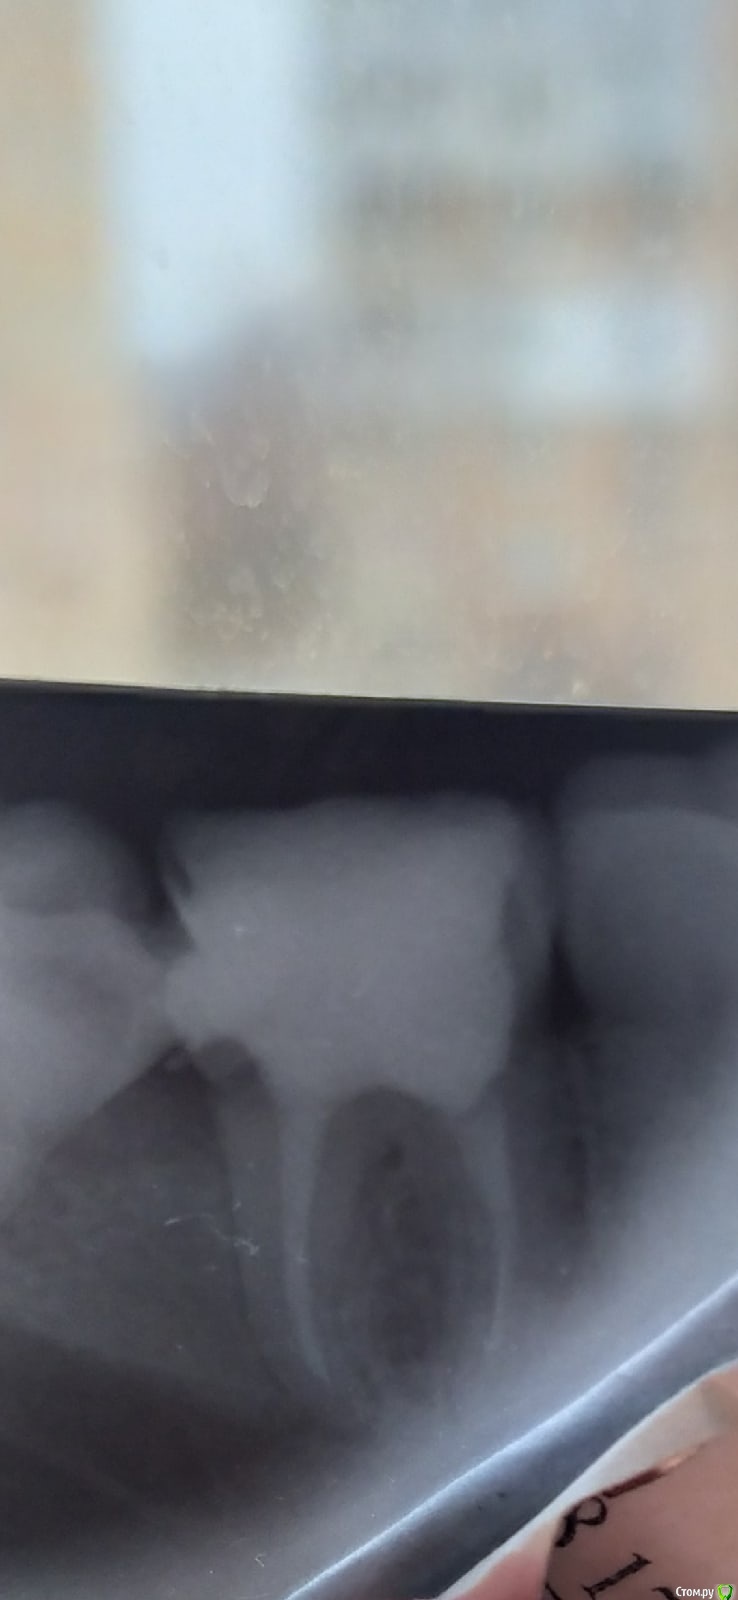

Goldi_V Опубликовано 3 февраля, 2021 Поделиться Опубликовано 3 февраля, 2021 (изменено) Добрый день, подскажите есть ли обломок инструмента в корне зуба, если да, то реально ли его достать? Зуб пока не беспокоит, но на корнях есть киста или гранулема, и его рекомендовали удалить, аргументируя тем, что там обломок и пройти каналы не получиться. Заранее спасибо. Изменено 3 февраля, 2021 пользователем Goldi_V Ссылка на комментарий

red_butler Опубликовано 3 февраля, 2021 Поделиться Опубликовано 3 февраля, 2021 качество снимка не позволяет ответить. Но в первую очередь удаляйте зуб мудрости Ссылка на комментарий